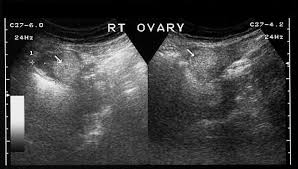

Sonographic Assessment Of Ovarian Cysts And Masses Chapter 8 Gynaecological Ultrasound Scanning from static.cambridge.org I was also diagnosed with diverticulosis following a ct a year before final diagnosis of stage 3 ovarian cancer. Can 19mm ovarian dermoid cyst be mistaken (misdiagnosed) with any another cysts? However, as women, this is something we need to be talking about. Malignant ovarian cysts are only seen in rare cases, with the benign being the most common of them all. A healthy ovary and one from a woman with pcos. Hi, my gyno told me that i had a dermoid cyst, even after my ca 125 test results were 2274. If you have a history of breast or ovarian cancer in your family, tell your ob/gyn so they can check for symptoms early on. They are often harmless and require no treatment.

February 2, 2016 at 1:10 pm. The mature teratoma is by far the most common ovarian germ cell tumor. Ovarian dermoid cysts, or teratomas, are. 1 doctor answer • 5 doctors weighed in share Ovarian cysts of less than 1 centimeter (0.4 inches) in size are common in postmenopausal women, the vast majority of which will be benign. This isn't the same as cause cancer; I was also diagnosed with diverticulosis following a ct a year before final diagnosis of stage 3 ovarian cancer. It is often called a dermoid cyst because its lining is made up of tissue similar to skin (dermis). They are often harmless and require no treatment. Malignant ovarian cysts are only seen in rare cases, with the benign being the most common of them all. A healthy ovary and one from a woman with pcos. Over the weekend i traveled to my hometown to support my mom while she underwent hysterectomy surgery. I kept complaining of a pain in my right side, about where i thought my appendix would be.